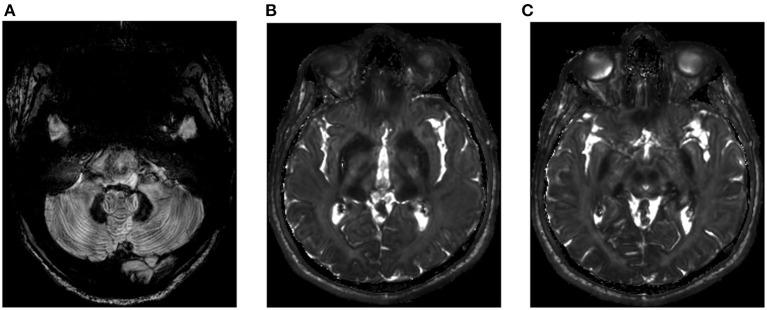

Aceruloplasminemia is a rare autosomal recessive inherited disorder. Mutations in the ceruloplasmin gene cause depressed ferroxidase activity leading to iron accumulation. The clinical phenotype is highly variable: anemia, retinopathy, diabetes mellitus, psychiatric disorders, and neurological symptoms including parkinsonian disorders and dementia are the main features of this disease. Characterized by high serum ferritin with low transferrin saturation, aceruloplasminemia uniquely combines brain, liver and systemic iron overload. We report here four new cases of aceruloplasminemia in a consanguineous North-African family. Genetic sequencing revealed a homozygous missense variant c.656T>A in exon 4 of the ceruloplasmin gene, which had been described previously as of "unknown significance" in the dbSNP database and never associated with ACP in the HGMD database. Ferroxidase activity was strongly depressed. Clinical manifestations varied among cases. The proband exhibited mild microcytic anemia, diabetes mellitus, psychosis and parkinsonism, whereas the other cases were asymptomatic or mildly anemic, although high serum ferritin and brain iron deposition were documented in all of them. Therapeutic management was complex. The proband started deferoxamine treatment when already symptomatic and he rapidly declined. In the asymptomatic cases, the treatment was associated with poor tolerance and was discontinued due to anemia requiring red blood cell transfusion. Our series illustrates the need for new therapeutic approaches to aceruloplasminemia.

无铜蓝蛋白血症是一种罕见的常染色体隐性遗传性疾病。铜蓝蛋白基因突变导致铁氧化酶活性降低,进而引起铁蓄积。其临床表型高度可变:贫血、视网膜病变、糖尿病、精神障碍以及包括帕金森氏症和痴呆症在内的神经症状是该疾病的主要特征。无铜蓝蛋白血症以血清铁蛋白升高和转铁蛋白饱和度降低为特征,独特地合并了脑、肝和全身铁过载。我们在此报告一个北非近亲家庭中的4例无铜蓝蛋白血症新病例。基因测序显示,铜蓝蛋白基因第4外显子存在纯合错义变异c.656T>A,该变异在dbSNP数据库中先前被描述为“意义不明”,在HGMD数据库中从未与无铜蓝蛋白血症相关联。铁氧化酶活性严重降低。各病例的临床表现各不相同。先证者表现为轻度小细胞贫血、糖尿病、精神病和帕金森症,而其他病例无症状或轻度贫血,尽管所有病例均记录有高血清铁蛋白和脑铁沉积。治疗管理很复杂。先证者在出现症状时开始使用去铁胺治疗,但病情迅速恶化。在无症状病例中,治疗耐受性差,因贫血需要输血而停药。我们的系列病例表明,需要针对无铜蓝蛋白血症探索新的治疗方法。